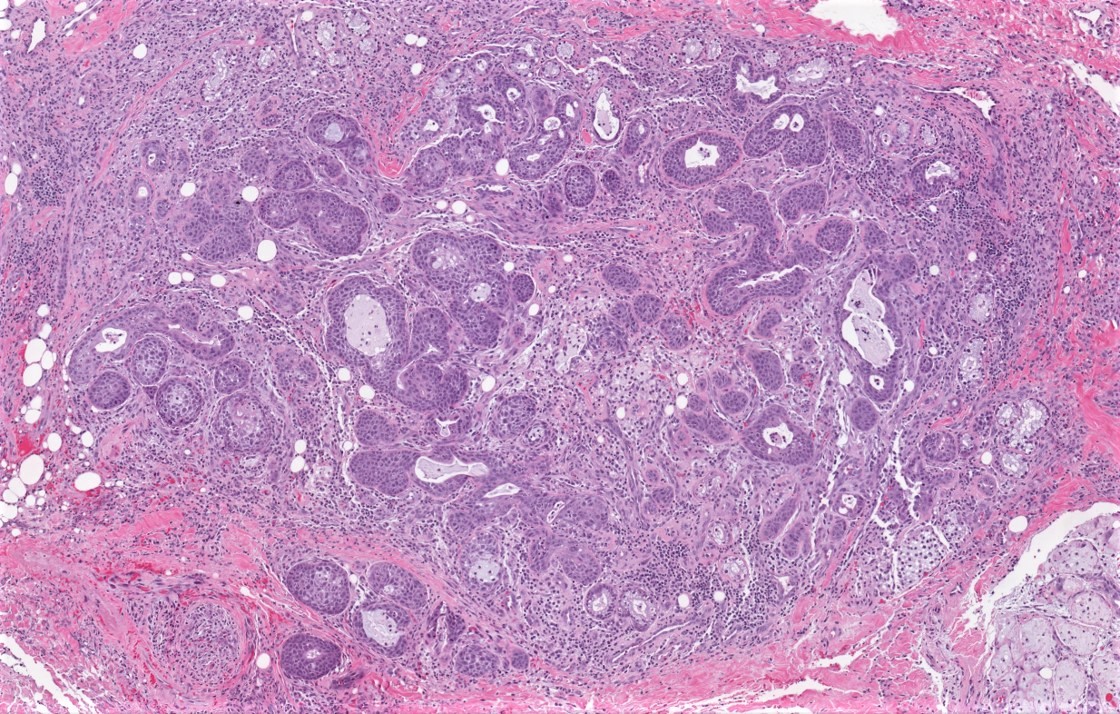

Microscopic (histologic) description

- Squamous metaplasia of ductal structures and acini with preservation of the salivary lobular architecture is an essential feature, according to World Health Organization (see WHO classification-oral cavity & oropharynx)

- Necrosis / infarction of acini characterized by loss of nuclei and cell borders with or without zones of spilled mucin

- Pseudoepitheliomatous hyperplasia with generally bland cytology or keratinocytic regenerative atypia

- Reactive, myxocollagenous background stroma

- Surface ulceration, granulation tissue and subacute inflammation may be present

- Has been conceptualized by 5 histologic stages of development and evolution: infarction, sequestration, ulceration, repair and healing (Int J Oral Surg 1982;11:283)

Microscopic (histologic) images